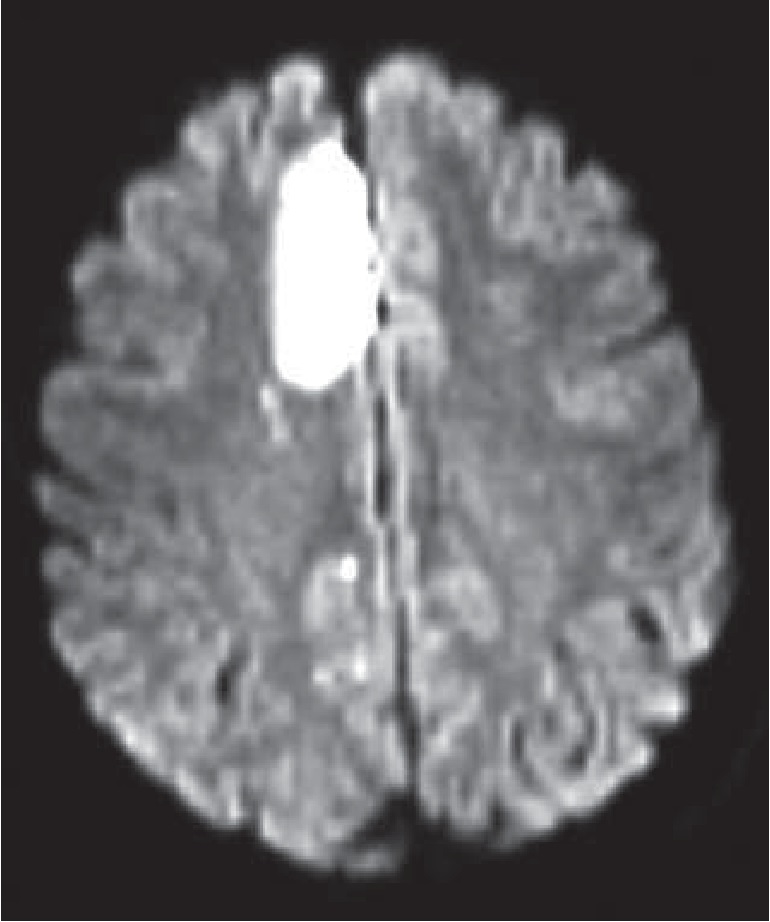

Объем зоны измененного сигнала варьировал от 50 до 10500 мм3 (Me=675 мм3). В одном случае формирование ОИП сопровождалось развитием транзиторного очагового двигательного дефицита (рис. 2). У данной пациентки с диссекционной аневризмой А2 сегмента правой ПМА выполнена эмболизация купола аневризмы в условиях стент-ассистенции. Интраоперационно проходимость перикаллезной артерии была сохранена, но через 6 часов после операции развился контралатеральный нижний монопарез. При контрольной ангиографии диагностирован тромбоз перикаллезной артерии в зоне стента с коллатеральным заполнением дистальных сегментов перикаллезной и каллозо-маргинальной артерий. Селективное и системное введение ингибиторов IIb/IIIa гликопротеиновых рецепторов тромбоцитов не привело к восстановлению кровотока. В течение недели после операции наблюдался монопарез в правой ноге. На фоне проводимой терапии двигательные расстройства полностью регрессировали в течение недели. При определении ментального статуса, по данным MoCA, до вмешательства результат составил 28 баллов. В послеоперационном периоде больная сделала на одну ошибку меньше в задании на отсроченное повторение слов и суммарно набрала 29 баллов. Таким образом, развитие ишемического осложнения не отразилось на состоянии высших психических функций пациентки.

Рис 2. Послеоперационная МР-томограмма головы пациентки, у которой развился транзиторный очаговый двигательный дефицит после внутрисосудистой окклюзии аневризмы ПМА